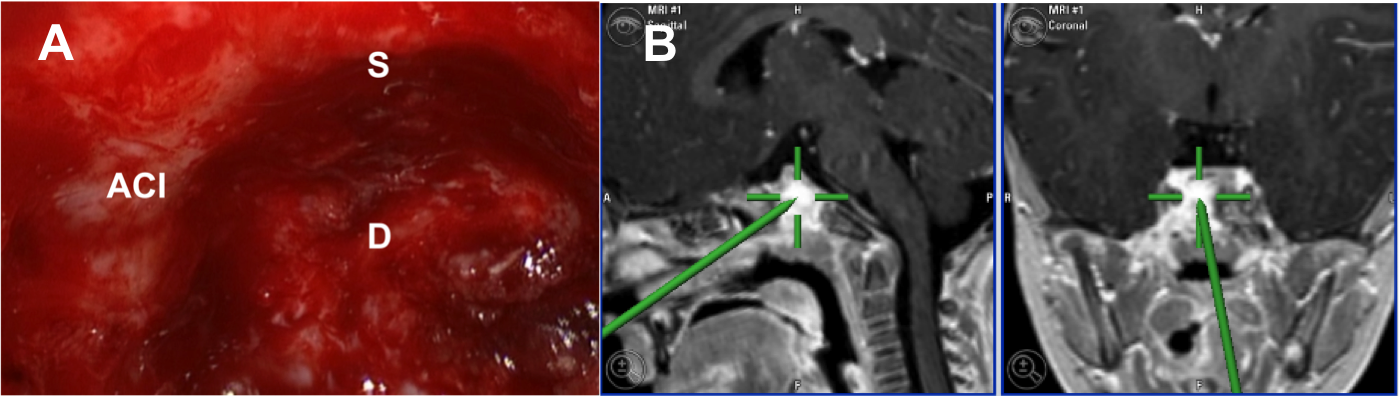

Introducción: La cirugía endoscópica endonasal se ha convertido en una herramienta fundamental para el manejo de patologías que comprometen la base de cráneo. En casos bien seleccionados, estas técnicas permiten resecciones quirúrgicas con una menor morbilidad sin comprometer los principios oncológicos de resección. Con el desarrollo de instrumental especializado, nuevas tecnologías y la experiencia de los cirujanos, la cirugía endoscópica endonasal se usa cada vez más en cirugía de base de cráneo en niños.

Diseño: Estudio observacional descriptivo de tipo serie de casos. Metodología: se describe la experiencia con pacientes pediátricos llevados a cirugía endoscópica endonasal para manejo de tumores de base de cráneo en el Instituto Nacional de Cancerología entre julio de 2014 y diciembre de 2016.

Resultados: Fueron intervenidos 8 pacientes entre los 2 y 14 años, con una edad promedio de nueve años y un seguimiento promedio de 16 meses. En el 75% se hizo una resección total del tumor. Un paciente requirió una reintervención y un paciente fue sometido a radiocirugía post-operatoria. 1 paciente falleció a pesar de múltiples intervenciones, quimioterapia y radioterapia.

Conclusión: La cirugía endoscópica endonasal para tumores de base de cráneo puede ser utilizada de forma segura en los pacientes pediátricos, es una técnica que en casos bien seleccionados pueden ofrecer excelentes resultados disminuyendo la morbilidad y complicaciones de las técnicas abiertas.

Herrera-Vivas A, Ospina-Díaz JA, Téllez-Cortéz PA, Feo- Lee O. Abordaje endoscópico transnasal para resección de tumores de la base de cráneo : nuestra experiencia. Acta otorrinolaringol. cir. cabeza cuello. 2012;125–32.

Chivukula S, Koutourousiou M, Snyderman CH, Fernandez- Miranda JC, Gardner PA, Tyler-Kabara EC. Endoscopic endonasal skull base surgery in the pediatric population. J Neurosurg Pediatr. 2013;11(3):227–41.